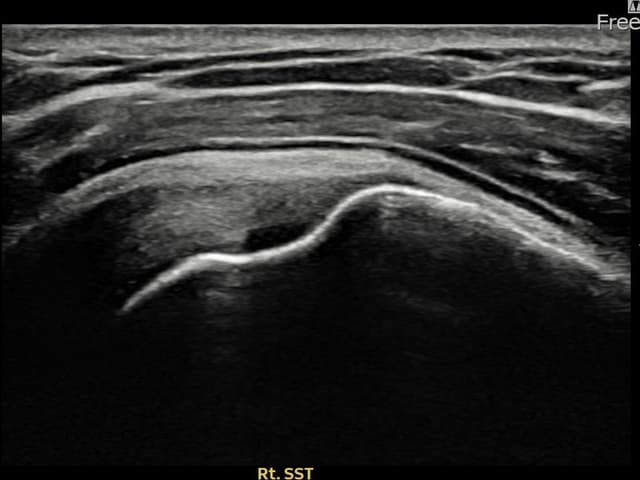

左侧 冈上肌腱 石灰化肌腱炎

9mm × 7mm